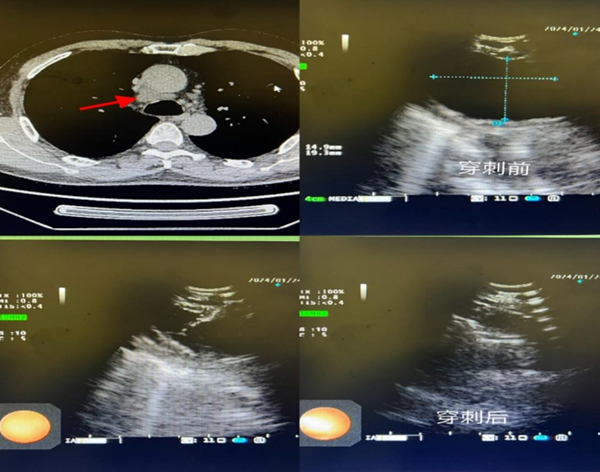

7.多学科合作

2024年, 呼吸团队与病理科、超声科、麻醉科、血管外科、微创肝胆、消化内科、耳鼻喉科等多学科多次合作。在间质性肺病、复杂高位气道狭窄、气管食管瘘等方面积累了丰富经验,极大提高了相关复杂疾病的诊疗能力。